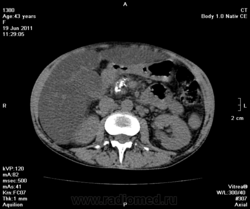

на фоне хр.калькулезного панкреатита опухоль головки поджелудочной железы, распространение на ворота печени, очень подозрительно на инвазию портальной вены и портальную гипертензию. Печень увеличена, гиподенсна, и если не ошибаюсь, цирроз.

Да, цирроз выставил, хотя конечно не такой уж он и показательный, нежели обычно с правильной атрофией и бугристыми контурами. На счет портальной вены тоже засомневался (на нативе прям как одно целое) и рекомендовал контраст, хотя, наверное, тут скорее эгоистический интерес.

Ну еще желчный пузырь и нефроптоз справа (за счет увеличенного вертикального размера печени).

а в желчном камешки, тут я их зажал показать)

и хр. холецистопанкреатит в анамнезе, как мы уточнили - калькулезный;-)

По-моему в печени жировой гепатоз. А контрастирование в этом случае обязательно.

Как прилежный ученик, я понимаю Вас, что основных то признаков нет - как со стороны селезенки (должного проявления портальной гипертензии), снижение плотности паренхимы печени (хотя фиброзные тяжи и тем более узлы должны бы давать повышенную плотность), отсутствие асцита! или хотя бы малого количества жидкости, отсутствие атрофических изменений и т.д...